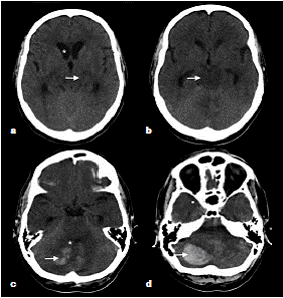

En los exámenes de laboratorio, se encontró compromiso de la función renal (cuadro 1), en tanto que en la tomografía computadorizada simple se evidenció un hematoma en el hemisferio cerebeloso derecho de 9,2 ml con compresión del IV ventrículo e hidrocefalia secundaria, además de hipodensidad a nivel de puente (figura 1).

En la tomografía computadorizada de control se observó persistencia de la hipodensidad de la región mesencefálica, así como cambios por la craniectomía suboccipital y el drenaje del hematoma cerebeloso derecho (figura 2). Debido a la persistencia del deterioro clínico, se hizo una resonancia magnética en la cual se encontraron múltiples eventos isquémicos (edema citotóxico) que afectaban especialmente los territorios de ambas arterias cerebrales posteriores y de la arteria cerebral media, y el territorio limítrofe profundo de dichas arterias; la hipodensidad tomográfica en el mesencéfalo y en el puente correspondía a edema vasogénico (figura 3).